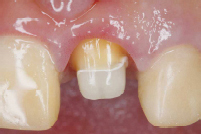

使用例

治療中

写真提供:坪田デンタルクリニック坪田有史先生